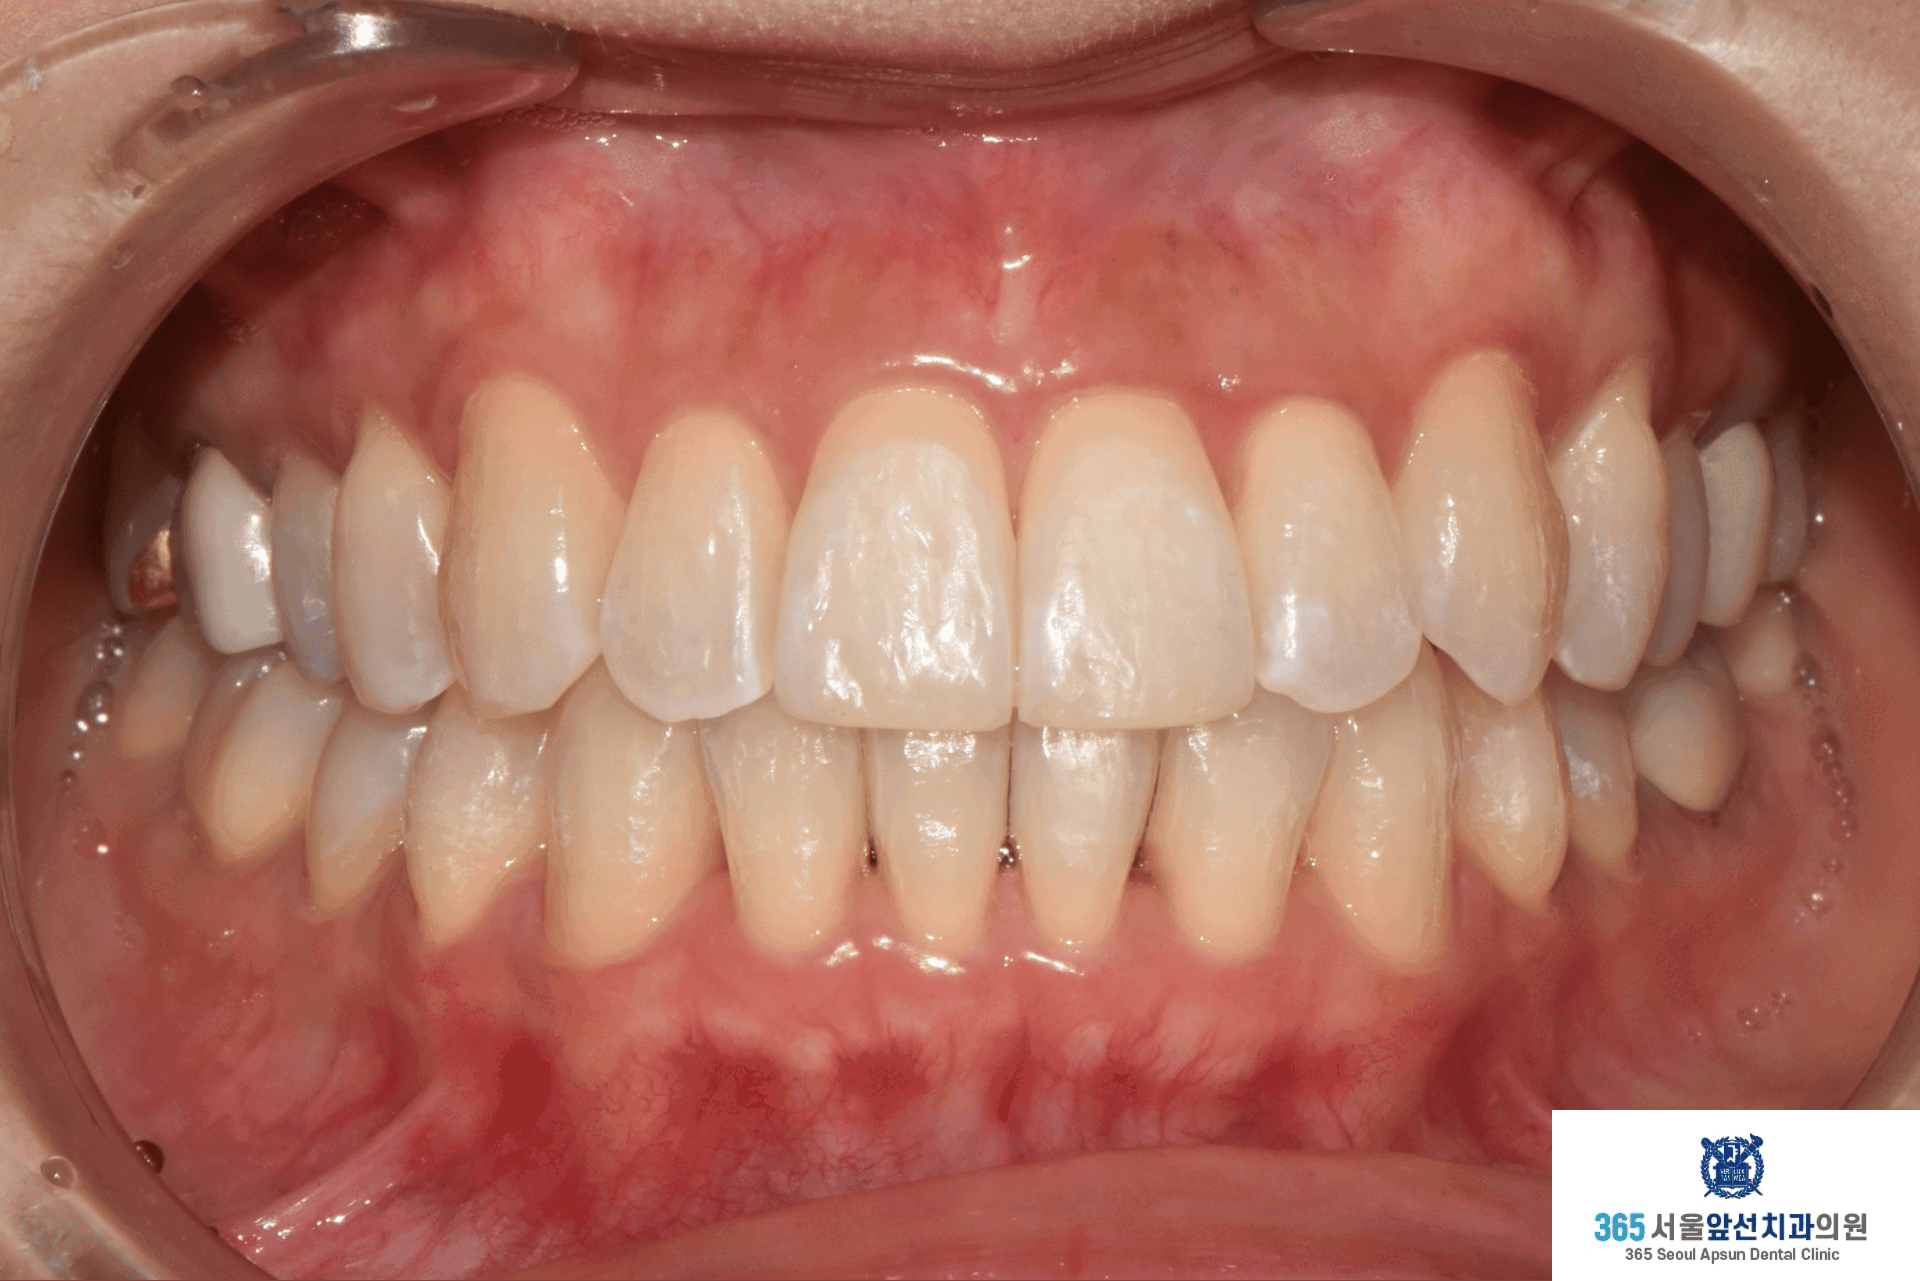

촬영일시 : 2025.12.16. 3월 12일 치료를 개시하여 12월 16일에 교정치료를 종료하였으며 총 9개월의 치료기간이 소요되었습니다. 치열이 가지런하게 배열되었고 목표하였던 견치의 1급 관계 회복, 앞니의 수평 피개 감소, 정중선 불일치 개선이 완료되었습니다. 환자분께서 치료를 열심히 따라와주셔서 치료가 깔끔하게 잘 마무리되었습니다. ![]() 촬영일시 : 2024.11.26. / 2025.12.16. 촬영일시 : 2024.11.26. / 2025.12.16. 투명교정이 기존의 부착식 교정장치보다 효과가 떨어지지는 않는지 여쭤보시는 환자분들이 종종 계십니다. 투명교정으로도 이상적인 치료 결과를 낼 수 있다는 예로 본 증례를 소개드렸습니다. 투명교정치료는 하루 20시간 이상의 착용이 필요하여 환자와 의료진이 함께 만들어가는 치료입니다. 부착식 장치에 비하여 위생 관리가 용이하며 협점막이 편안하고 심미적입니다. 감사합니다!